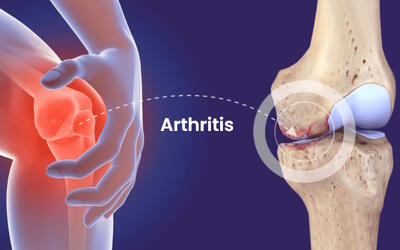

آرتروز و مشکلات ستون فقرات از جمله بیماری های مزمن دستگاه اسکلتی-عضلانی هستند که به دلیل تغییرات دژنراتیو در مفاصل، مهره ها و دیسک های بین مهره ای بروز می

رئیس دانشگاه علوم پزشکی شهید بهشتی با هشدار درباره افزایش بیماریهای اسکلتی و عضلانی، گفت: مقصد نهایی بسیاری از بیماریها به مشکلات عضلانی و اسکلتی ختم میشود که نیاز به توجه بیشتری دارد.